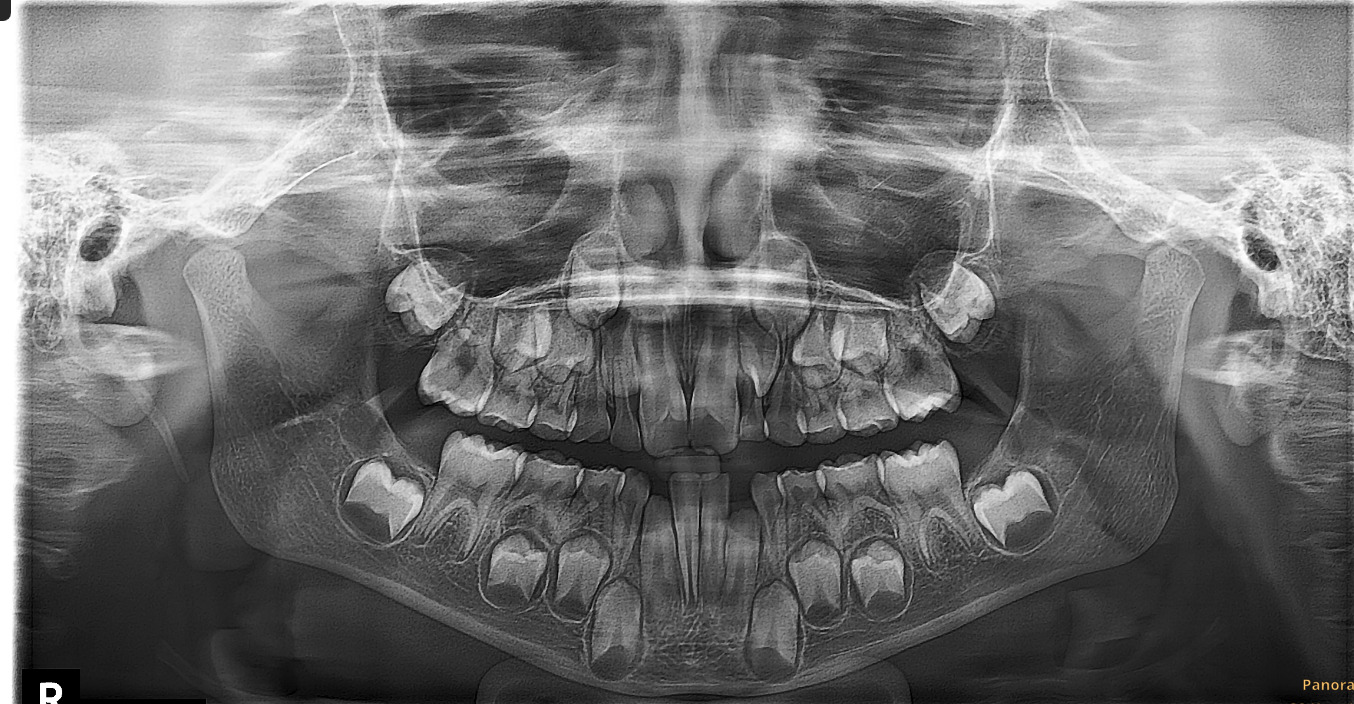

Примеры ортопантомограмм и их анатомия

Раздел: Фотоэссе